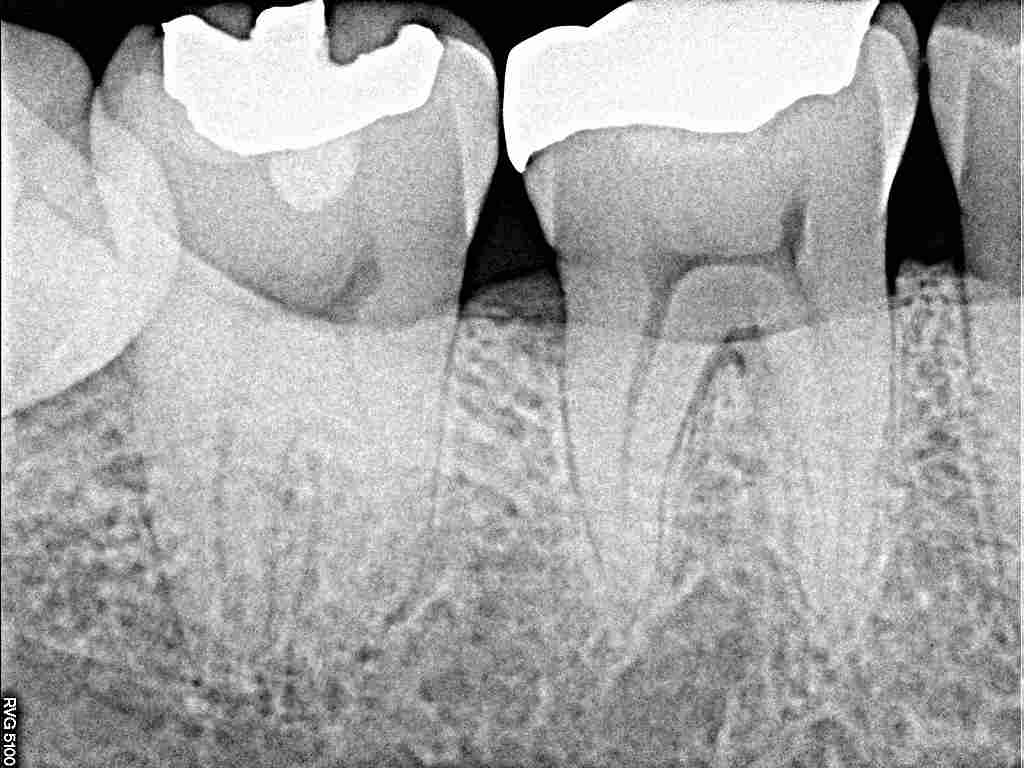

下顎 右下の完全埋伏歯の難抜歯 時々違和感があるそうです|お知らせ |広島市安佐南区の歯科医院 下顎 右下の完全埋伏歯の難抜歯 時々違和感があるそうです トップ お知らせ・ブログ お知らせ 下顎 右下の完全埋伏歯の難抜歯 時々違和感があるそうです 下顎 右下の完全埋伏歯の難抜歯 時々違和感があるそうです ここに親不知が存在しています 小帯のようなものが存在 デンタルではわかりにくいです パノラマレントゲンになります このように開けています 親知らずは歯石だらけで炎症も強いです 切開もなく抜歯しています 縫合して終了となります Web診療予約 初めての方へ 選ばれ続ける理由 院内設備について 歯が痛いしみる一般歯科 歯がぐらぐらする歯周病 健康な歯を保ちたい予防歯科 子供の虫歯予防をしたい小児歯科 銀歯をセラミックに審美歯科 白い歯を目指しませんか?ホワイトニング 矯正専門医がいるので安心矯正歯科 抜けた歯を補いたいインプラント・入れ歯 医院案内 スタッフ紹介 メリィハウス歯科クリニックオフィシャルホームページ ラベンダー歯科クリニックオフィシャルホームページ お知らせ・ブログ ホーム 診療科目 一般歯科 歯周病治療 予防治療 小児歯科 審美治療 ホワイトニング 矯正歯科 入れ歯・インプラント マウスピース矯正 初めての方へ 院長・スタッフ 設備紹介 医院案内・アクセス メニューを閉じる